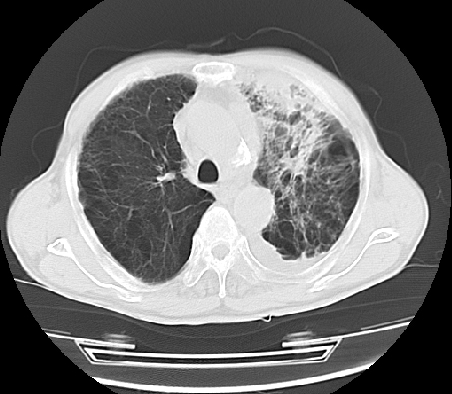

以下是引用ct诊断高手在2009-5-29 13:50:00的发言:[br]考虑左侧中央型肺癌,阻塞性肺炎伴肺不张。纵隔淋巴结转移。慢支 肺间质纤维化肺气肿。左侧胸腔积液。左侧肋骨转移?

以下是引用hhcckk在2009-5-29 14:58:00的发言:[br]左上周围型肺癌,左肺门、纵隔淋巴结转移,左侧胸腔积液,左侧肋骨转移[br]